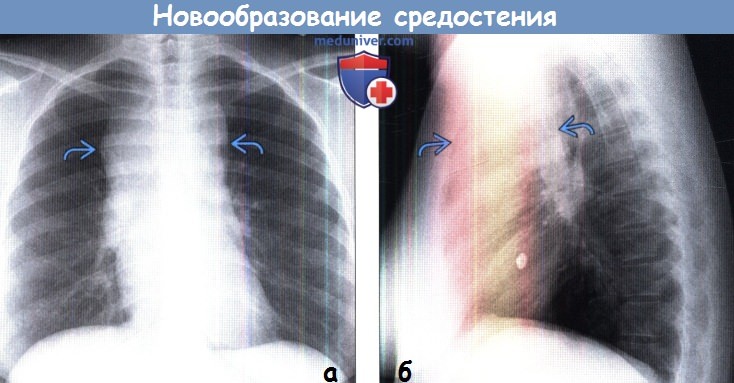

Рентгеновские снимки тератомы средостения: Диагностика и лечение